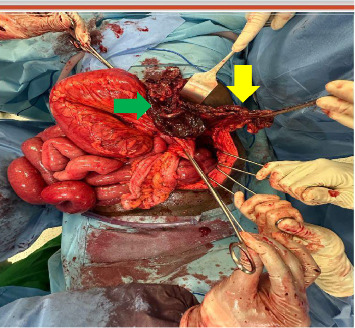

创伤后膈疝(PTDH)被定义为由创伤引起的膈病理缺损引起的腹内器官向胸腔内迁移。PTDH是一种罕见的疾病,发生在所有胸腹损伤的3%-7%。大约14.6%的PTDH病例在初次创伤后数月至数年出现。延迟PTDH并发肠梗阻和穿孔的病例极为罕见,据报道患病率为0.17%-6%。在非洲,在过去三十年中记录的延迟PTDH病例不到10例。尽管有已发表的报告,但目前尚无管理PTDH的既定实践指南。在这里,我们提出一个延迟PTDH的情况下,表现为急性肠梗阻12年后枪伤到胸部。这种情况导致了致命的术后结果。本病例强调了临床医生在有创伤史的急性肠梗阻患者中考虑PTDH的迫切需要,并强调了紧急手术治疗以防止致命并发症的重要性。

Post-traumatic diaphragmatic hernia (PTDH) is defined as the migration of intra-abdominal organs into the chest through a pathological defect in the diaphragm caused by trauma. PTDH is a rare condition, occurring in 3%-7% of all thoracoabdominal injuries. Approximately 14.6% of PTDH cases present months to years after the initial trauma. Cases of delayed PTDH complicated by bowel obstruction and perforation are exceedingly uncommon, with a reported prevalence of 0.17%-6%. In Africa, fewer than 10 cases of delayed PTDH have been documented over the past three decades. Despite the availability of published reports, there are no established practice guidelines for managing PTDH. Here, we present a case of delayed PTDH that manifested as acute bowel obstruction 12 years after a gunshot wound to the chest. The condition led to a fatal postoperative outcome. This case highlights the critical need for clinicians to consider PTDH in patients with a history of trauma presenting with acute bowel obstruction and underscores the importance of urgent surgical management to prevent fatal complications.